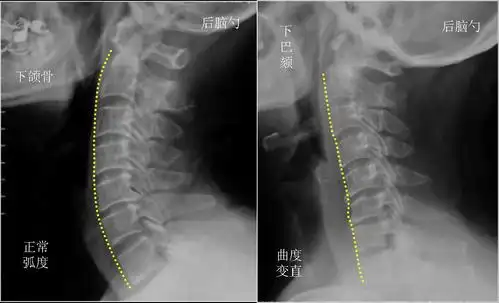

颈椎,腰椎生理曲度变直是怎么一回事

这个图片可以让我们认识颈椎是有生理曲度的